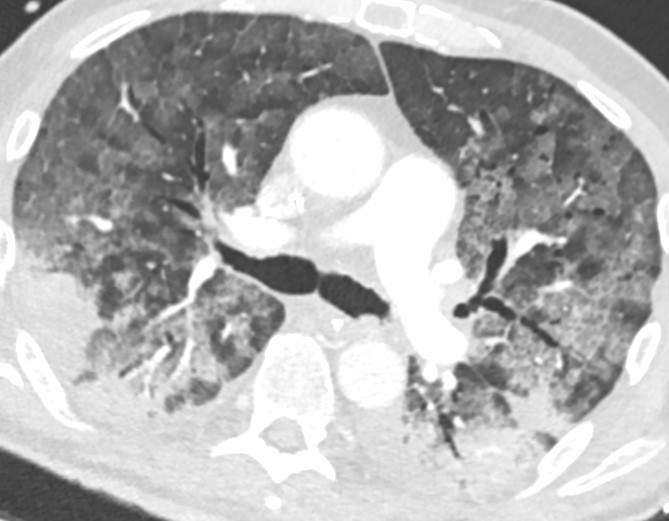

Respiratorbehandlingen forløp relativt ukomplisert første uken, og han ble ekstubert dag 7 etter innleggelse. Neste dag ble han igjen intubert grunnet respirasjonssvikt. Den respiratoriske situasjonen forverret seg, og både oksygeneringen og ventilasjonen ble dårligere (figur 1a–b). Kliniske funn var nå forenlig med klassisk akutt lungesviktsyndrom (ARDS) med stive lunger, og CT thorax dag 15 viste betydelige lungeforandringer og perifere lungeemboluser (figur 2).

For å klare å ventilere pasienten tilstrekkelig, ble han i en lengre periode dypt sedert og muskelrelaksert, med både boluser og kontinuerlig infusjon med muskelrelakserende midler over flere dager. Det ble forsøkt mageleie i flere omganger, uten bedring, og pasienten måtte snus tilbake i ryggleie grunnet vanskelig ventilering med betydelig økning av pCO2 (figur 1).